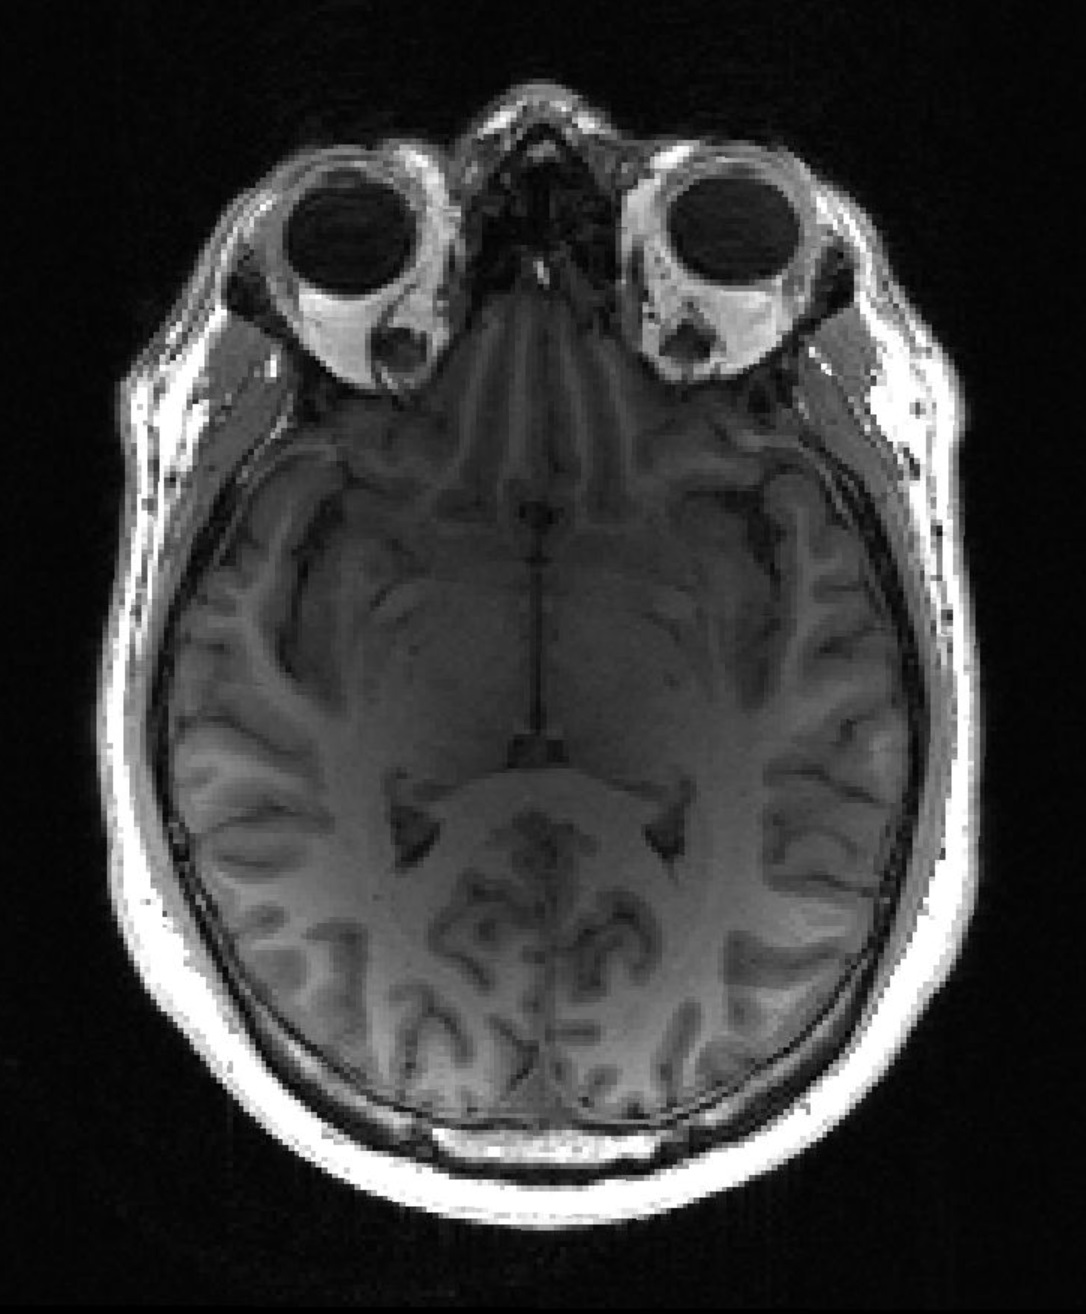

Медицинский центр Эразма в Роттердаме (Нидерланды) в ходе совместных исследований с Intel Labs и Медицинской школой Перельмана при университете Пенсильвании нашел способ выявлять злокачественные опухоли мозга на более ранней стадии. Для этого исследователи использовали новую технологию — федеративное обучение, объединяющее в себе машинное обучение и искусственный интеллект. В рамках этого проекта ученые показали, что можно на треть улучшить обнаружение опухолей мозга.

Это крупнейшее на сегодня медицинское исследование с использованием новейших технологий, в котором использовался беспрецедентный глобальный набор данных с участием 71 учреждения, расположенных на шести континентах.

Автоматическое обнаружение опухолей — важный шаг для персонализации и мониторинга лечения, и для разработки этой методики было необходимо использовать данные из разных учреждений. Благодаря этому сотрудничеству мы смогли легко это сделать, сохранив при этом контроль над данными в наших собственных сетях.